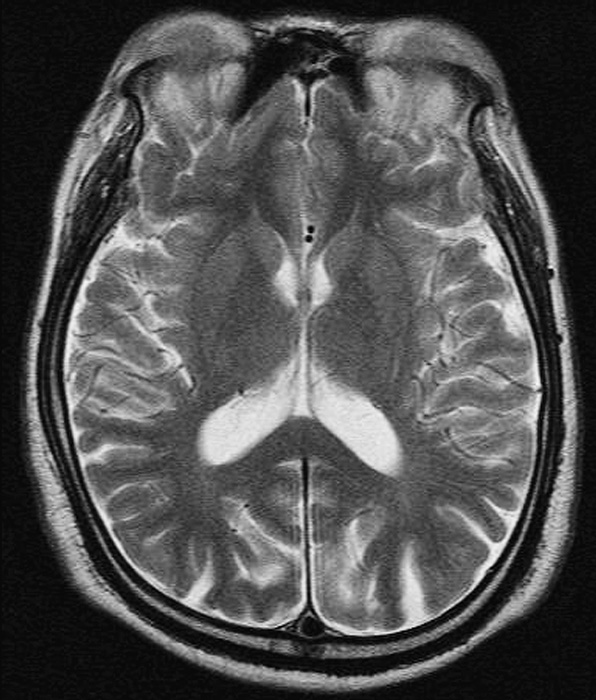

Typical Grade 0 case, a 55-year-old male who had no T2-elongated spots in any of the axial T2-weighted images.